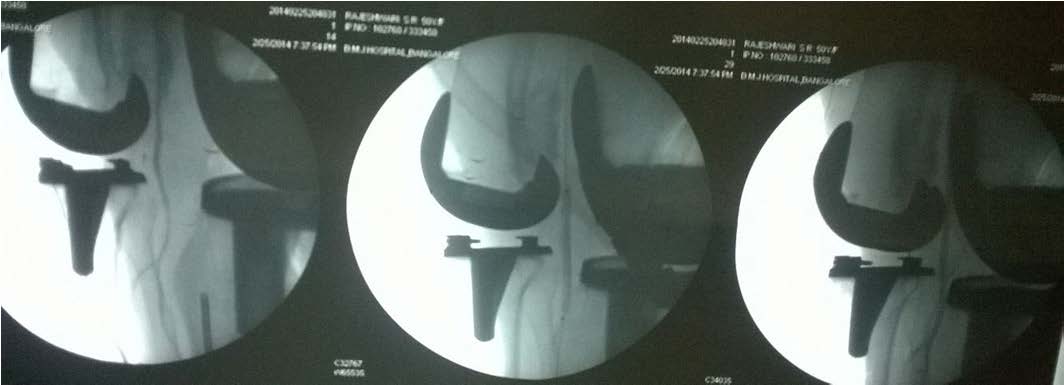

Postoperatively Epidural infusion (Bupivacaine 0.125% and Clonidine 2 μg/ml) was started at 6 ml per hour. Night rounds patient was comfortable with epidural analgesia with bilateral equal pulsations in foot. On next day morning patient complained of severe pain in left calf and numbness in left lower limb, mainly below the knee joint and on examination the left dorsalis pedis and posterior tibial artery pulsation were absent with normal left femoral artery pulsation. Postoperative x-ray in both anterior and lateral view was satisfactory. Toes on the left leg were slightly cooler than on the right and capillary refill time was prolonged. Colour Doppler examination was done which revealed no flow at the level of the knee and below [Table/Fig-1]. Vascular surgeon was immediately consulted and patient was subjected to emergency angiogram followed by thrombectomy and fasciotomy by double incision technique under epidural analgesia on the same day (2nd postoperative day) [Table/Fig-2] and patient was shifted to intensive care unit for next two days with intravenous antibiotics plus heparin infusion, post embolectomy angiogram showed good flow [Table/Fig-3]. On 3rd postoperative day patient had good pulsation on periphery.

Angiography of left lower limb, demonstrating the decreased flow below the popliteal atherosclerotic plaque

Angiography of left lower limb, post angioplasty flow has increased, with good flow of blood distally